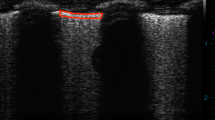

ABSTRACT: The passive exhalation flow-volume plots of preterm lambs exhibit curvature. To explain this curvature, we proposed two mathematical models that could predict the measured passive exhalation flow-volume data well. One model takes into account the flow and volume dependence of resistance and compliance. The second model emphasizes the time dependence of lung mechanics and considers the respiratory system viscoelastic properties and the analogy of the lung to two electronic resistor-capacitor circuits connected in parallel. We attempted to determine which of the two models is more valid by analyzing passive exhalation flow-volume data that were obtained while briefly obstructing flow midway through deflation. In 14 preterm lambs (130 d gestation), the flow of exhaled gas increased from 76 ± 35 mL/s when measured just before obstruction to 90 + 30 mL/s when measured immediately after release of the obstruction (p < 0.0001). This finding suggests that a time-dependent phenomenon was taking place during obstruction and is inconsistent with the model based upon the flow and volume dependence of resistance and compliance. We made similar measurements in four near-term (143–146 d gestation) and four full-term lambs (9–12 d of age). Their flow-volume curves were relatively linear, and they showed no increases in flow after removal of the obstruction. The results of this study strongly suggest that time-dependent phenomena caused the curvilin earity in the passive exhalation flow-volume plots of preterm lambs. We suspect that the time-dependent phenomena is associated with the premature lung and with parenchymal lung disease. The models of viscoelastance and of parallel inhomogeneities in the lung are consistent with our observations.